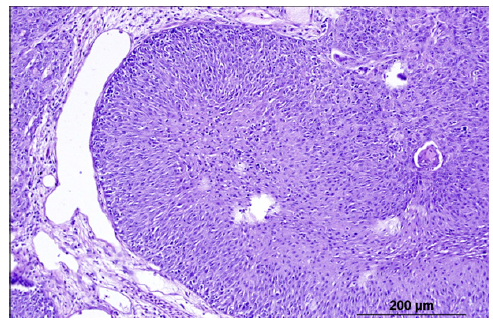

An example of such an individualized curative intervention was performed on an adult specimen of Cyprinus rubrofuscus var. koi that had a tumorous mass on the dorsal aspect of the head, spherical-cap shaped with a diameter of approximately 4 cm and a height of 3 cm (Figure 1). The carp was sedated by immersion in water containing clove oil at 0.03 ml·L-1, the mass was ligated and subsequently excised using surgical suture material (Figure 2). Throughout the procedure, the fish was kept in water. The growth was a pedunculated structure closely attached to the skin, with the short stalk having a cross-sectional area of approximately 1 cm2. After removal of the tumour, severe arterial bleeding occurred from the centre of the surgical wound. The bleeding was controlled by compression, followed by closure of the bleeding vessel using absorbable surgical skin glue. The carp was transferred to a tank shortly after the procedure and was feeding again the following day. It showed no behavioural abnormalities. The healing process was monitored, with granulation tissue formation and proliferation of the covering epithelium observed over time (Figure 3). Histologically, the tumour was identified as a papilloma (Figure 4). In the present case, tumour development could not be associated with environmental contamination or elevated xenobiotic levels in the water. The carp was kept in a garden pond supplied exclusively with municipal tap water, which is regularly monitored and meets drinking-water standards. This reduces the likelihood that chemical pollutants, heavy metals, or other harmful substances played a role in tumour induction. Nevertheless, even in controlled environments, other non-chemical stressors such as fluctuating water temperature, suboptimal pond hygiene, mechanical irritation, or social stress may contribute to epithelial hyperplasia or neoplastic transformation in susceptible fish [6]. Therefore, while environmental xenobiotics can be important cofactors in tumour development in aquatic animals, their involvement in this case appears unlikely, suggesting that other factors such as viral aetiology or individual immunological predisposition may have been more influential.

Figure 4:Histological examination classified the tumour as a papilloma.